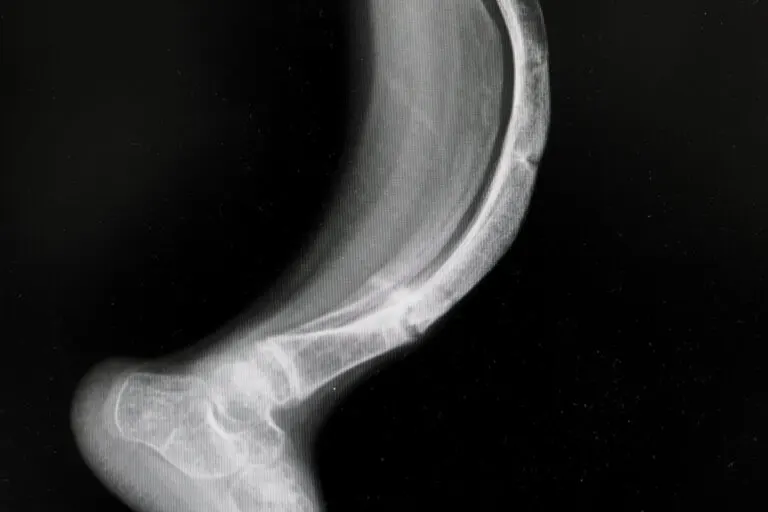

La osteogénesis imperfecta es una enfermedad en los huesos que tiene su origen en una anomalía genética, lo que deriva en la generación insuficiente de colágeno (la proteína mayoritaria del cuerpo humano).

Se trata de un compendio de trastornos hereditarios que tienen un rango notable de afectación, debido a que pueden desencadenarse pocas fracturas o decenas si se trata de una presentación grave.

- Radiografías.